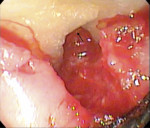

While the small incisions and minimal tissue reflection contributed to the superior results obtained using these techniques, visualization remained a primary limiting factor of MIS until the recent introduction of the videoscope (MicroSight, Q-Optics Inc, www.q-optics.com) described by Harrel et al. The videoscope is a high-definition digital camera placed on the end of a flexible tube 2.7 mm in diameter featuring a carbon fiber retractor that may be rotated to aid in flap reflection and a gas-shield that prevents blood and contamination from obscuring the camera, allowing improved visualization of the defect once inserted into the surgical site. Images taken with the videoscope are seen on a nearby surgical monitor at 20X to 60X magnification (Figure 12). Clinically, the enhanced visualization achieved with the videoscope facilitates improved defect debridement and root planing.10 Figure 13 shows the hand piece containing the videoscope that is used during surgery. A sample case treated with the videoscope and MIS (ie, VMIS) can be seen in Figure 1 through Figure 11.

To highlight the capabilities of VMIS, Harrel et al15 presented a clinical outcomes case series that featured an original cohort of 30 patients with 110 qualifying sites treated with VMIS and followed for at least 36 months. For inclusion, patients had an isolated interproximal area of periodontal destruction with a PD of at least 5 mm, CAL of at least 2 mm, and radiographic evidence of bone loss on periapical radiographs following initial nonsurgical therapy. The authors obtained minimally invasive surgical access, debrided the sites and planed the roots, biomodified root surfaces with 24% EDTA, and grafted with EMD and DFDBA. As before, flaps were repositioned and sutured while closure was ensured by digital pressure applied to the papilla tips with moist sterile gauze. Clinical measurements were recorded at baseline, 6 months, 12 months, and at least 36 months post-operatively. All 30 patients were available for the 6-month data, 18 patients were available for the 12-month data, and 14 patients were available for the 36-month or greater data, with an average post-operative time of 46.5 months ranging from 36 to 58 months. Since no statistically significant difference was found between measurements obtained for 1-wall, 2-wall, and 3-wall defects, data was combined for patient-level measurements of all surgical sites for the 14 patients who completed the study through the final evaluation. Results for these 14 patients revealed that a mean baseline PD of 6.41 ± 0.66 mm improved to 2.81 ± 0.58 mm at 6 months, 2.18 ± 0.58 mm at 12 months, and 2.61 ± 0.88 mm at 36 months+ for a mean improvement from baseline to 36 months+ of 3.80 ± 1.18 mm (P < 0.001). Measurements for gingival recession revealed that a mean gingival recession at baseline of 0.74 ± 0.95 mm improved to 0.69 ± 0.98 mm at 6 months, 0.31 ± 0.39 mm at 12 months, and 0.38 ± 0.67 mm at 36 months+ for a mean improvement (ie, gain in soft tissue height) of 0.36 ± 0.64 mm (P = 0.057) from baseline to the final post-operative visit. Finally, measurements for CAL improved from a mean baseline of 7.14 ± 0.97 mm to 3.50 ± 1.15 mm at 6 months, 2.49 ± 0.62 mm at 12 months, and 2.99 ± 1.05 mm at the 36 months+ post-operative for a mean improvement of 4.16 ± 1.18 mm (P < 0.001) from baseline to the final post-operative evaluation. Results of a visual analogue scale (VAS) patient survey indicated that only one patient experienced minor pain on the day of surgery while a different patient noted minor pain at the one and two week post-operative visits. All other patients reported no pain on the day of surgery or at any of the subsequent appointments.15 Additionally, all patients were satisfied with their treatment and said they would undergo the procedure again if indicated and would recommend the treatment to a friend.17 The results of the VAS survey highlighted one of the most important advantages to MIS, namely that patients generally experience minimal to no discomfort and have a high degree of satisfaction with the procedure.